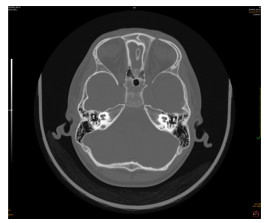

神经超声联合神经磁共振成像在吉兰-巴雷综合征诊断中的意义及机制研究

时鹏, 武心语, 怀玉水, 宋宏伟, 年娣

2025, 23(8): 1292-1297. doi: 10.16766/j.cnki.issn.1674-4152.004118

摘要:

目的  探讨神经超声联合神经磁共振成像在吉兰-巴雷综合征(GBS)患者诊断中的作用及机制。  方法  选取蚌埠医科大学第一附属医院2021年10月—2025年2月被诊断为GBS的患者43例,另选取24例健康体检者作为对照组。依据临床症状、体征及神经电生理检查将患者分为急性炎性脱髓鞘性多发神经根神经病(AIDP)和急性运动轴突性神经病(AMAN)两个亚型组,采用神经超声测量颈神经根、肢体周围神经横断面积(CSA);神经磁共振成像测量颈神经根、腰骶神经根CSA;吉兰-巴雷综合征残疾评分量表(GDSS)评估GBS患者神经功能缺失程度,分析CSA与神经缺损程度之间的相关性;收集外周静脉血,ELISA试剂盒测定外周血中细胞焦亡炎性因子水平。  结果  与对照组相比,AIDP组和AMAN组神经根、肢体周围神经增粗,CSA升高,其中神经超声示3组C5、C6比较差异均有统计学意义(H=20.216,P < 0.001;H=12.452,P=0.002);磁共振成像结果显示,与AMAN组和健康对照组相比, AIDP组患者C4~C8、L3~S1的CSA显著升高,差异均有统计学意义(P < 0.01);周围神经CSA与神经功能缺损程度呈正相关关系(P < 0.05);GBS患者外周血焦亡炎性因子水平较对照组升高,差异有统计学意义(P < 0.05)。  结论  GBS患者神经根和周围神经CSA值升高和神经功能缺损可能与焦亡途径激活导致的炎症级联反应有关,联合神经影像学和炎性因子检测有助于GBS的早期诊断,为GBS诊疗提供新思路。